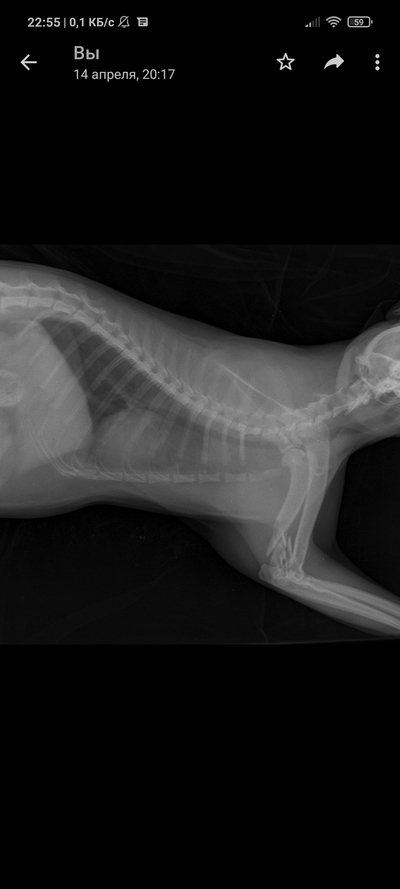

Так уж получилось что я ветеринарный врач, работаю в интенсивной терапии - принимаю и лечу самых тяжелых животных. На днях ближе к ночи прибегает женщина с котом, который шлёпнулся перед ней на улице. При осмотре выясняется что кот в шоке - лежит на боку, без давления, температуры, у него сломаны передние лапы, лицо, пневмоторакс и немного жидкости в брюшной полости (вероятно кровь). Женщина оставляет двадцатку на первые сутки и идет искать хозяина, кот помещается в стационар для стабилизации состояния. Всю ночь я ебусь с этим котом, вывожу его из шока, спускаю ему пневмоторакс, грею, обезболы льются рекой, к утру кот похож на кота, а не на покойника - начал садиться, ползать, полизал еду.

В общем, четвертый день от падения, полет нормальный, кот начал есть сам, а я иду на смену, ждите новостей, думаю скоро будет пост про то, как мы оперируем животных, в частности собираем ходули герою этой истории 😁